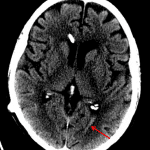

Age: 80

Sex: Female

Indication: Posttraumatic headache

- High density material layering in the left occipital horn and in the right cerebellopontine angle cistern, concerning for acute hemorrhage

- Left parieto-occipital scalp hematoma without subjacent calvarial fracture

- Right frontal approach ventriculostomy catheter terminates in the right frontal horn with hypoattenuation along the catheter track

- Diffuse cerebral volume loss with scattered areas of subcortical and periventricular white matter hypoattenuation

- Trace intraventricular and subarachnoid hemorrhage

High density material layering in the left occipital horn and in the right cerebellopontine angle cistern, concerning for acute hemorrhage. No mass effect or hydrocephalus.

Left parieto-occipital scalp hematoma without subjacent calvarial fracture. Partial opacification of the left mastoid air cells and middle ear without definite temporal bone fracture. This finding could alternatively relate to inflammatory or infectious otomastoiditis.

Right frontal approach ventriculostomy catheter terminates in the right frontal horn with hypoattenuation along the catheter track likely representing gliosis.

Diffuse cerebral volume loss with scattered areas of subcortical and periventricular white matter hypoattenuation which though nonspecific likely represents sequela of chronic microvascular ischemia in this age group.